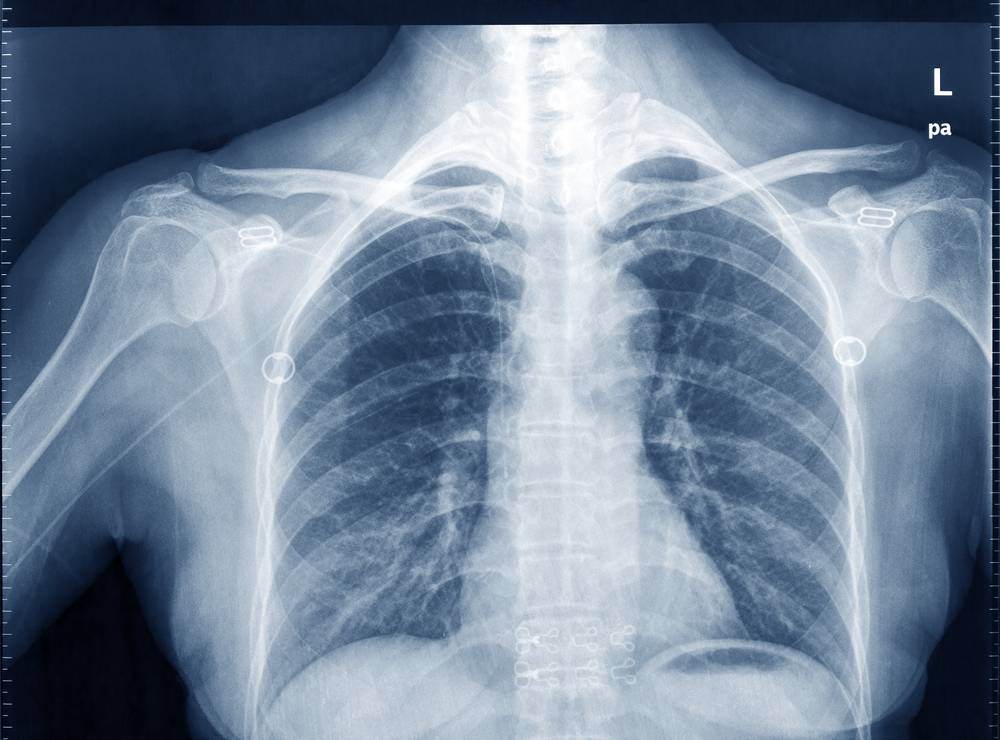

흉부 X레이 사진을 사용해 나이를 추정, 만성질환을 잡아내는 인공지능(AI) 모델이 나왔다. 치명적인 여러 질병을 조기에 발견할 수 있는 기술로 주목받고 있다.

오사카 도립대학교 연구진이 흉부 방사선 사진을 사용해 연령을 정확하게 추정하는 AI 모델을 개발했으며, AI 추정 연령과 실제 연령 사이에 차이가 있는 경우 만성 질환의 경고 신호일 수 있다는 것을 발견했다고 과학 전문 스터디파인즈가 17일(현지시간) 보도했다.

연구진은 먼저 건강한 개인의 흉부 방사선 사진을 사용해 나이를 추정하기 위해 AI 모델을 구축했다. 그다음 이 모델을 알려진 질병이 있는 환자의 방사선 사진에 적용하여 AI 추정 연령과 특정 질병 간의 관계를 분석했다.

2008~2021년 3만6000명 이상의 건강한 지원자로부터 6만7000개 이상의 흉부 방사선 사진을 얻었다. 이러한 방사선 사진 데이터는 연령 추정을 위한 AI 모델의 개발, 학습 및 테스트에 사용했다.